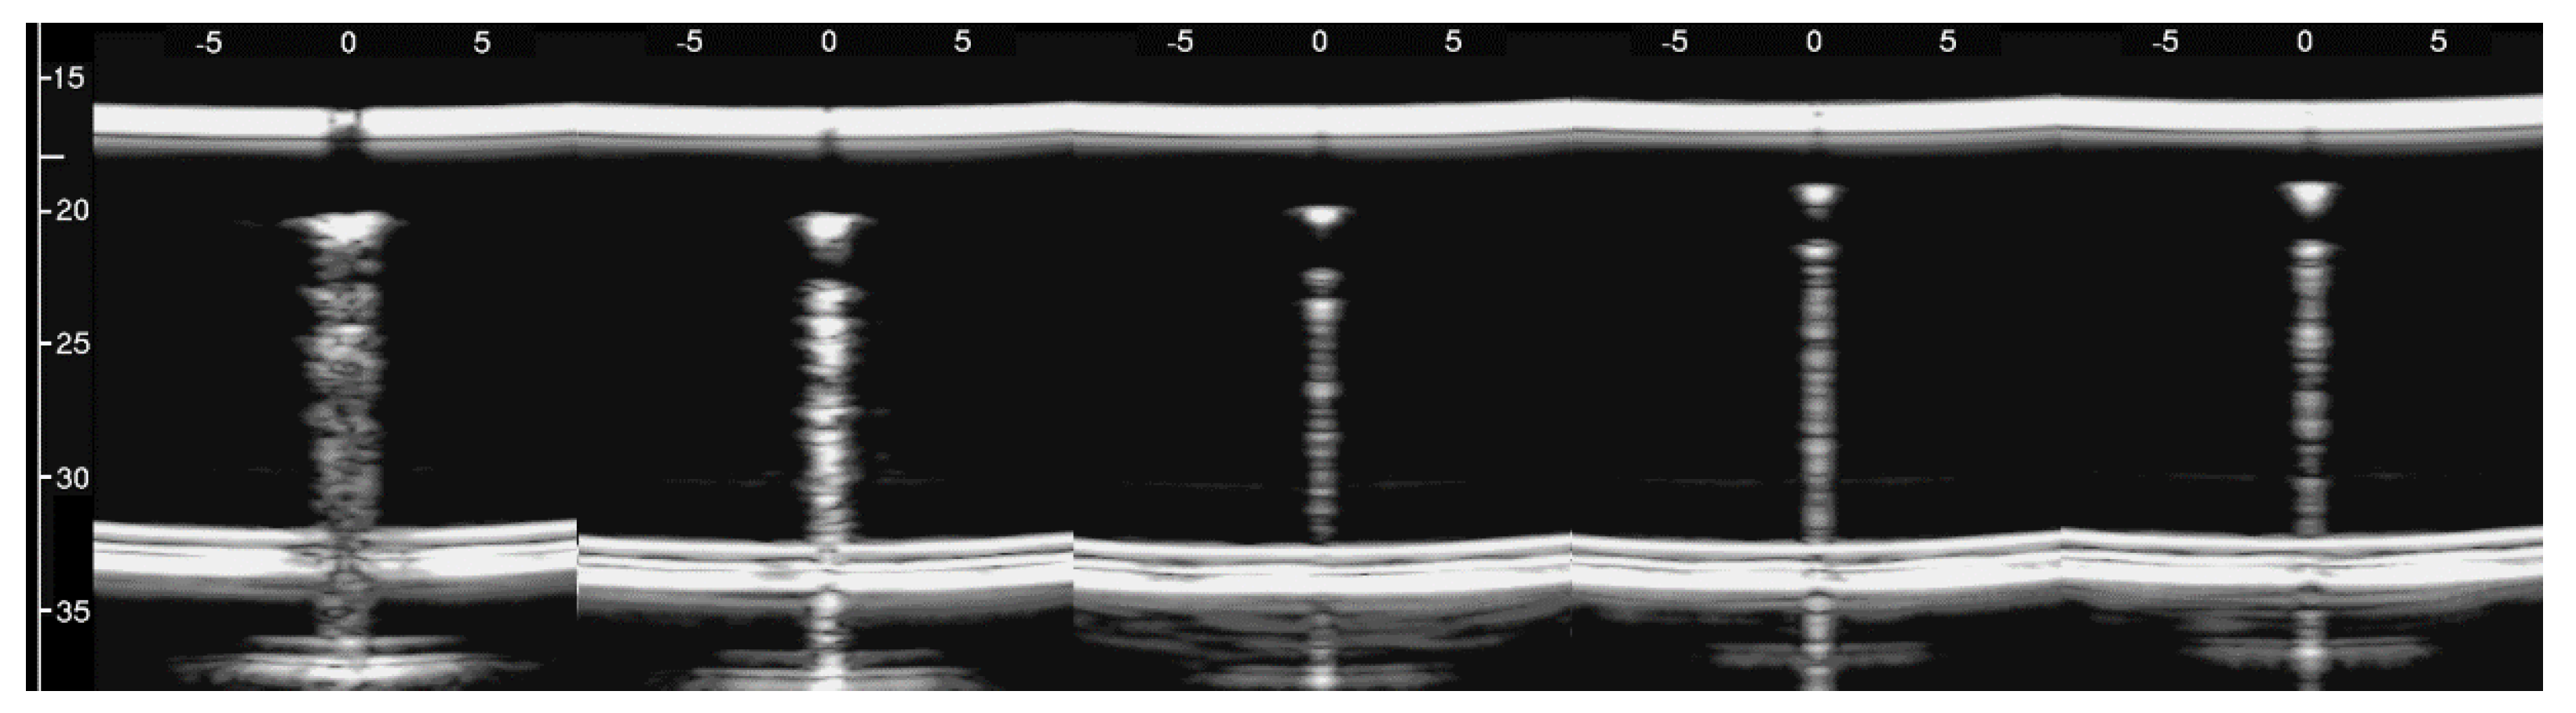

Figure 8, from left to right, shows the details of the artifacts which were obtained on agar cusps with a thickness t equal to 2, 1, 0.5, 0.3, and 0.1 mm, respectively (see Figure 3). A distance of about 4 mm, between the upper polyethylene film and the first reflection generated by the agar cusps, is derived from the figure, according to the assumed propagation speed of 1500 m/s. This means that the US pulse, once it has been transmitted to the ridge of the agar cusps, propagates through the agar sample and reaches the lower polyethylene film before being reflected towards the probe. Figure 8 shows how modulated B-lines are obtained when the thickness t of the coupling section is equal to 0.5, 0.3, and 0.1 mm, and how confused artifacts are obtained when the latter increases. A slightly confused modulation was obtained when the thickness of the cusp ridge was equal to 1 mm. Modulated artifacts, such as those observed in cardiogenic pathologies, are finally obtained for the first time on deterministic phantoms, and they seem to be correlated to the size of the acoustic channel which links the acoustic trap to the chest wall.

Figure 8. From left to right, the figure shows the vertical artifacts which were obtained with models of agar cusps having a thickness t of the upper part equal to 2, 1, 0.5, 0.3, and 0.1 mm, respectively. The two thick white lines at the top and at the bottom of the images represent the reflection of the upper polyethylene film and its replica, respectively.